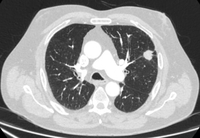

Cortes de tomografia computadorizada (TC) com exemplos de nódulos solitários semissólidos

Do acervo de Dr. George Tsaknis, MD, PhD, FRCP (Londres), MRQA, MAcadMEd, PGCert; usado com permissão